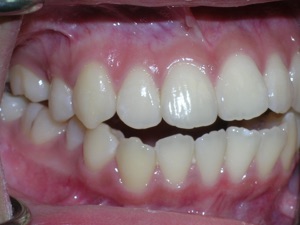

So here’s a case of an open bite, with a protrusion. There was a fair degree of crowding as well.

Here are the results.